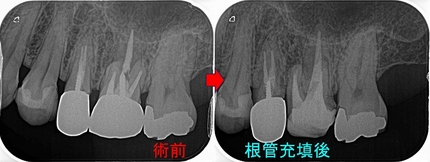

クラウンが取れた歯の根管治療

基本的に私は歯を長持ちさせる為のポイントは「必要最小限の医療介入」だと思っています。

を過去に取った歯のクラウンのやり替えの際には、根尖病変さえ無ければわざわざ根管治療はしません。

ただ、経過を見させてもらっているとこういう判断をすることはあります。

患者さんは30代女性

昔から診させて頂いているかんじゃさんなのですが、被せ物が外れたということで来院

過去からのレントゲンを見ると

2025 EEdental FRI (1).jpg

口蓋根の根尖に前は無かった根尖病変が現れています。

患者さんに、レントゲンを見せてクラウンだけ入れてもまたすぐに外す必要が出てきそうだから

この歯に関しては一度根管治療からやり直した方がいいと説明

今回の歯、以前のブログで出したMB2ニッケルチタン形成法のケースでした。

術後

2025 EEdental FRI (2).jpg

4根ガッタパーチャー使用 レジンコア+仮歯まで

定期検診で来院してもらいました。

2025 EEdental FRI (3).jpg

綺麗に口蓋根の根尖病変は治ってくれています。

ついでに返信投影でレントゲンを撮らせてもらいました。

2025 EEdental FRI (4).jpg

綺麗に治ってくれたので、次にセラミッククラウンの治療に入って行きます。

このように根管治療に介入するしないは、私の場合病変のある・なしで判断することが殆どで

前の先生の治療が信用でいないとか、ガッタパーチャーが入っていないからという理由で根管治療をやり替えることは殆どありません。

根管治療は2回しか治療出来ない治療なので、歯を長く保存させるにはいつ根管治療介入に踏み切るか!?も重要なポイントだと思います!(^。^)